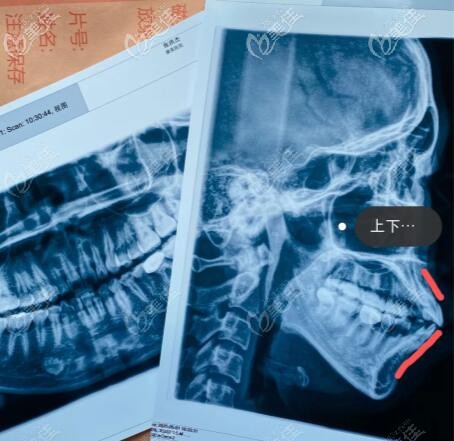

這是我骨性凸嘴做正頜手術(shù)一年半,一路看到自己側(cè)臉的變化我真的好開心,下巴內(nèi)收了7mm,嘴凸問題得到了有效改善,整個面型協(xié)調(diào)很多,后悔自己沒早點去做正頜手術(shù)。